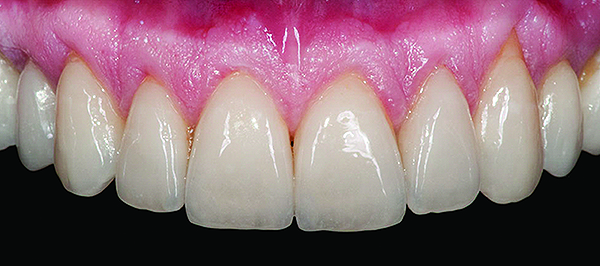

Fig 3. Preoperative (Fig 1), preparation (Fig 2), and final postoperative (Fig 3) images of a two-unit CL-I feldspathic veneer case.

Figure 3

Class I (CL-I) powder and liquid porcelains are created from materials primarily containing silicon dioxide and possess a glassy matrix and varying amounts of a crystalline phase within the glassy matrix (eg, Creation Porcelain, Jensen Dental, www.jensendental.com; Ceramco 3, DENTSPLY International, www.dentsply.com; EX-3, Kuraray Noritake Dental, Inc., www.kuraraynoritake.com). The CL-I group includes feldspathic porcelains, referred to as such because they were originally—and some continue to be—made from naturally occurring feldspars (ie, aluminosilicates composed of assorted quantities of potassium, sodium, barium, or calcium).9,17 Several feldspathic material options are available on the market today (eg, VITA VM 13, VITA Zahnfabrik, www.vita-zahnfabrik.com; Vintage Halo, Shofu, www.shofu.com) (Figure 1 through Figure 3).

CL-I materials are fabricated by hand (Figure 4); they are the most conservative and generally the most translucent ceramic materials, but they are also the weakest.9,10,18 The material’s high translucency and esthetics create the illusion of natural teeth.9 Powder/liquid porcelain materials are ideal for cases in which significant enamel remains and/or there is healthy tooth structure on the teeth (ie, 50% or more remaining enamel on the tooth), and 50% or more of the bonded subst rate is enamel, and 70% or more of the margin is in the enamel. Feldspathic porcelain restorations that are bonded to primarily enamel substrates have proven to be highly successful long term.19

Powder/liquid porcelains demonstrate high esthetics and workability, and because they can be layered very thinly and placed directly on the enamel, they are considered the most conservative of the metal-free ceramic classes.10 CL-I porcelains require a thickness of 0.2 mm to 0.3 mm for each shade change.20,21

This class of materials is generally indicated for anterior restorations but can also be used for the occasional bicuspid and rare molar, providing all parameters are at a very low risk level (Figure 5 and Figure 6).